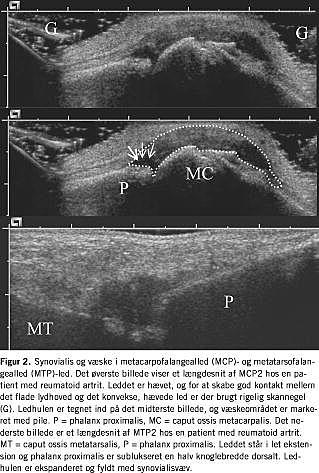

Synovialis' forhold omkring de fleste perifere og overfladenære led kan vurderes med ultralyd. Ved artrit og i mange tilfælde af artrose ses en tydelig hypertrofi af synovialis. De enkelte led har karakteristiske områder med en sådan hævelse af synovialis. Således vil synovialis over finger- eller tåled pose ud i omgivelserne over strækflader, formodentlig afhængig af mulighederne for udvidelse (Fig. 2 ). Ud over selve den hypertrofiske synovialis kan væskeansamlinger i mange tilfælde identificeres som ekkotomme strøg (Figur 2). Ganske svarende til den kliniske erfaring ses væskedannelsen mest udtalt i knæled, hvor fordelingen af ansamling i den suprapatellare reces og over ledlinjer kan afklares med UL-skanning. I hofteregionen kan man ved UL-skanning afsløre en fortykket synovialis, mens tilstedeværelsen af eventuel væskeansamling ofte først vil kunne afgøres i forbindelse med selve punkturen (Fig. 3 ). I disse led kan UL-vejledt aspiratio n give materiale til bakteriologisk differentialdiagnostik.

I knæled er der ligeledes gode muligheder for at undersøge for synovialishypertrofi, og man kan skelne ekssudater fra synovialisvæv [25]. En samtidig skanning af knæet bagpå afslører i talrige tilfælde Baker-cyster, som ofte går upåagtet hen ved en ren klinisk undersøgelse [26] (Figur 2). Differentialdiagnosen mellem dyb venøst tromboflebit og rumperet Baker-cyste er mulig med UL-skanning, og denne undersøgelse kan anbefales som rutine ved akutte smerter i læggen [27]. UL-skanning af menisker, korsbånd og forhold omkring brusk er mulig; men da ultralyd ikke kan passere knoglevæv, er man oftest udelukket fra at gennemse de relevante strukturer, og metoderne kan derfor næppe anbefales til anvendelse i daglig klinik [4, 28-30].